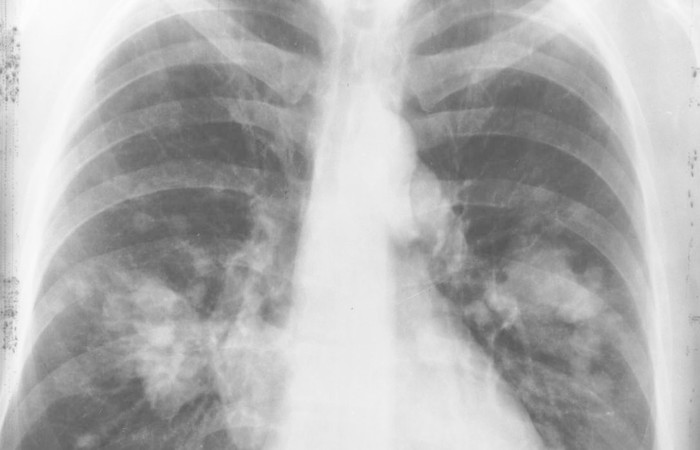

A psicóloga Lenise Amorim, de 41 anos, é um destes casos. “Em outubro de 2020, em plena pandemia, eu recebi o diagnóstico de câncer no pulmão, já localmente avançado e nessa ocasião eu tinha só 39 anos. Eu era completamente assintomática e não tinha nenhum histórico de tabagismo e também nunca convivi com pessoas que fumavam”, relata.

A descoberta ocorreu durante uma ressonância magnética para investigar um nódulo no pescoço que já estava ali há dez anos.

Segundo Prado, esse tipo de câncer normalmente é encontrado de forma não intencional por um exame solicitado por outro motivo.

“A gente viu bastante, durante a pandemia, porque, de certa forma, baixamos muito os limiares para solicitação de exames de imagem, como tomografia de tórax, para pacientes com sintomas respiratórios suspeitos para covid. Com isso, a gente teve muito diagnóstico incidental de nódulos pulmonares e muitas dessas lesões pequenas foram investigadas e diagnosticadas como câncer de pulmão.”

Ele acrescenta que é comum que essas doenças já sejam descobertas em estágios avançados. No caso de Lenise, era um estágio 3, de uma escala que vai até 4. Contudo, o tumor ainda estava localizado apenas no pulmão.